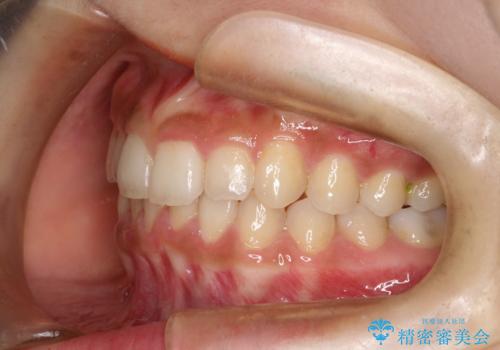

- 前歯のガタガタを主訴に来院された患者様です。

八重歯になっており、下顎の前歯が上顎の前歯に隠れてしまう、ディープバイトという状態でした。

インビザラインを使用して矯正する計画としました。